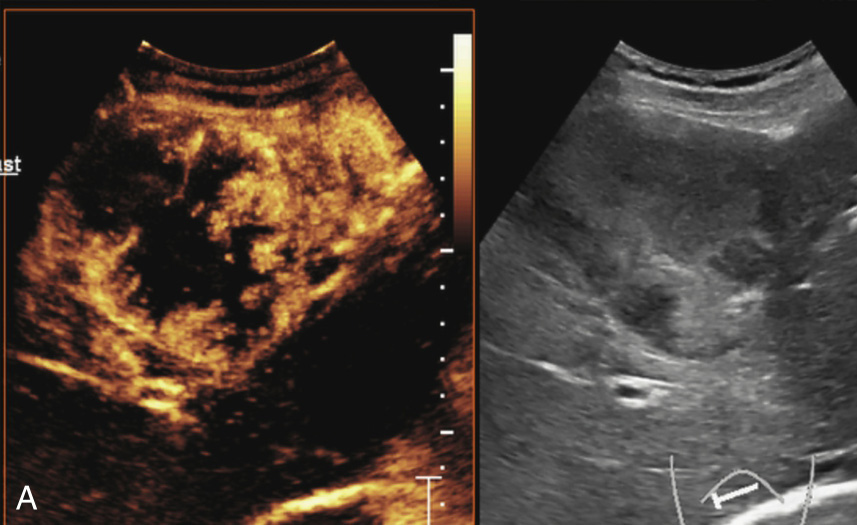

(5)超声造影:

动脉早期病灶呈周边环状增强或整体高增强,门脉早期病灶内造影剂消退呈低增强(图1-7-6)。

图1-7-6 胆管细胞癌超声造影图像

A.造影剂注入14s周边不规则环状增强;B.35s病灶内造影剂开始消退呈低增强

图1-7-6(续)

C、D.门脉期及延迟期造影剂持续消退呈低增强